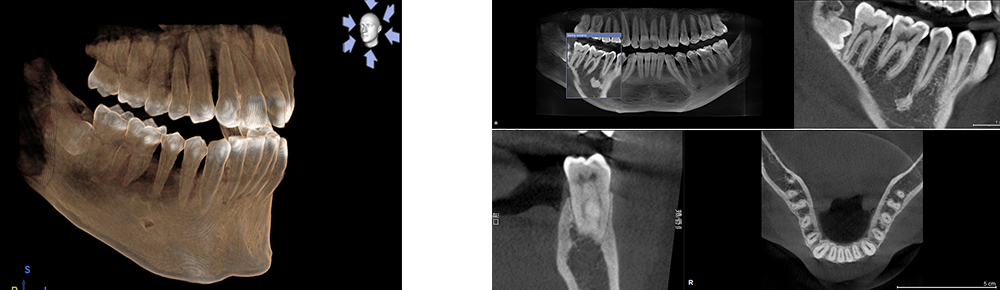

通常では歯の根の治療は、複数枚のレントゲン写真を撮影し、診断を行います。しかし、特に臼歯部の診断時にレントゲン画像だけでは診断が難しい場合があります。そのような通常のレントゲン撮影では分かりにくかったさまざまな部分を、CTで撮影した立体的画像ならより詳しく診断することができます。

問題部位が発見できなければ治療を行うことはできません。

精密な画像診断により問題部位を可視化することが可能になりました。

そのため、術前にCTで解剖をはっきり確認し、ニッケルチタンファイルという根管の解剖を破壊しない器具を使い、マイクロスコープで直接見て治療を行うことが大切になります。